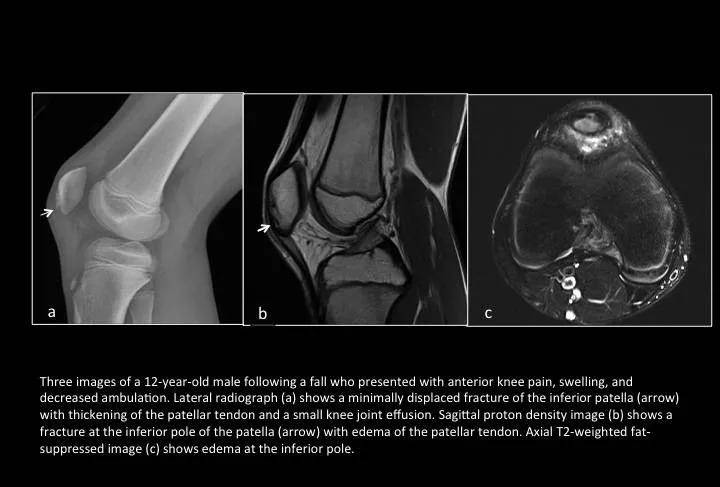

Fig. 18: Patellar sleeve avulsion fracture

图18:髌骨袖套状撕脱骨折

是儿童特有的一种髌骨骨折。因为髌骨软骨骨转化过程中的髌骨骺生长板,位于其骨化核周缘,骺板的增殖、肥大细胞带和初级钙化带薄弱,常不能耐受剪式应力而分离损伤。当膝关节处于半屈曲位股四头肌强烈收缩时,牵引髌骨向上,而髌韧带固定髌骨形成作用力和反作用力,髌骨下部的软骨受股四头肌强烈收缩而发生的撕脱性骨折,带有少量骨组织或无骨组织被拔除,呈套状。